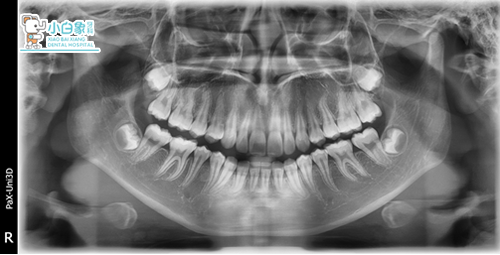

初诊时间:2016.01.26

结束时间:2017.12.31

QQ截图20180120141953.png

治疗前

QQ截图20180120142000.png

治疗后